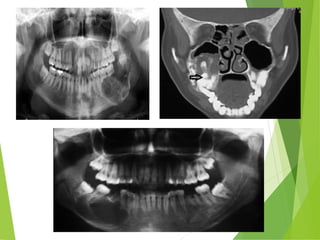

RADIOGRAPHIC FINDINGS

• Ameloblastomas are osteolytic & present as

unilocular or multilocular.

• Well circumscribed by bony radiopaque borders

• Margins are usually well defined & sclerotic

• Root resorption & tooth displacement.

• Displacement of the neurovascular bundle

• Cortex shows thinning and often severe expansion

• Involvement of the antrum is seen as an opacification.

PANORAMIC VIEW

(revealed a large multilocular radiolucent area extending from the 44

to the right coronoid process including the ascending ramus area)